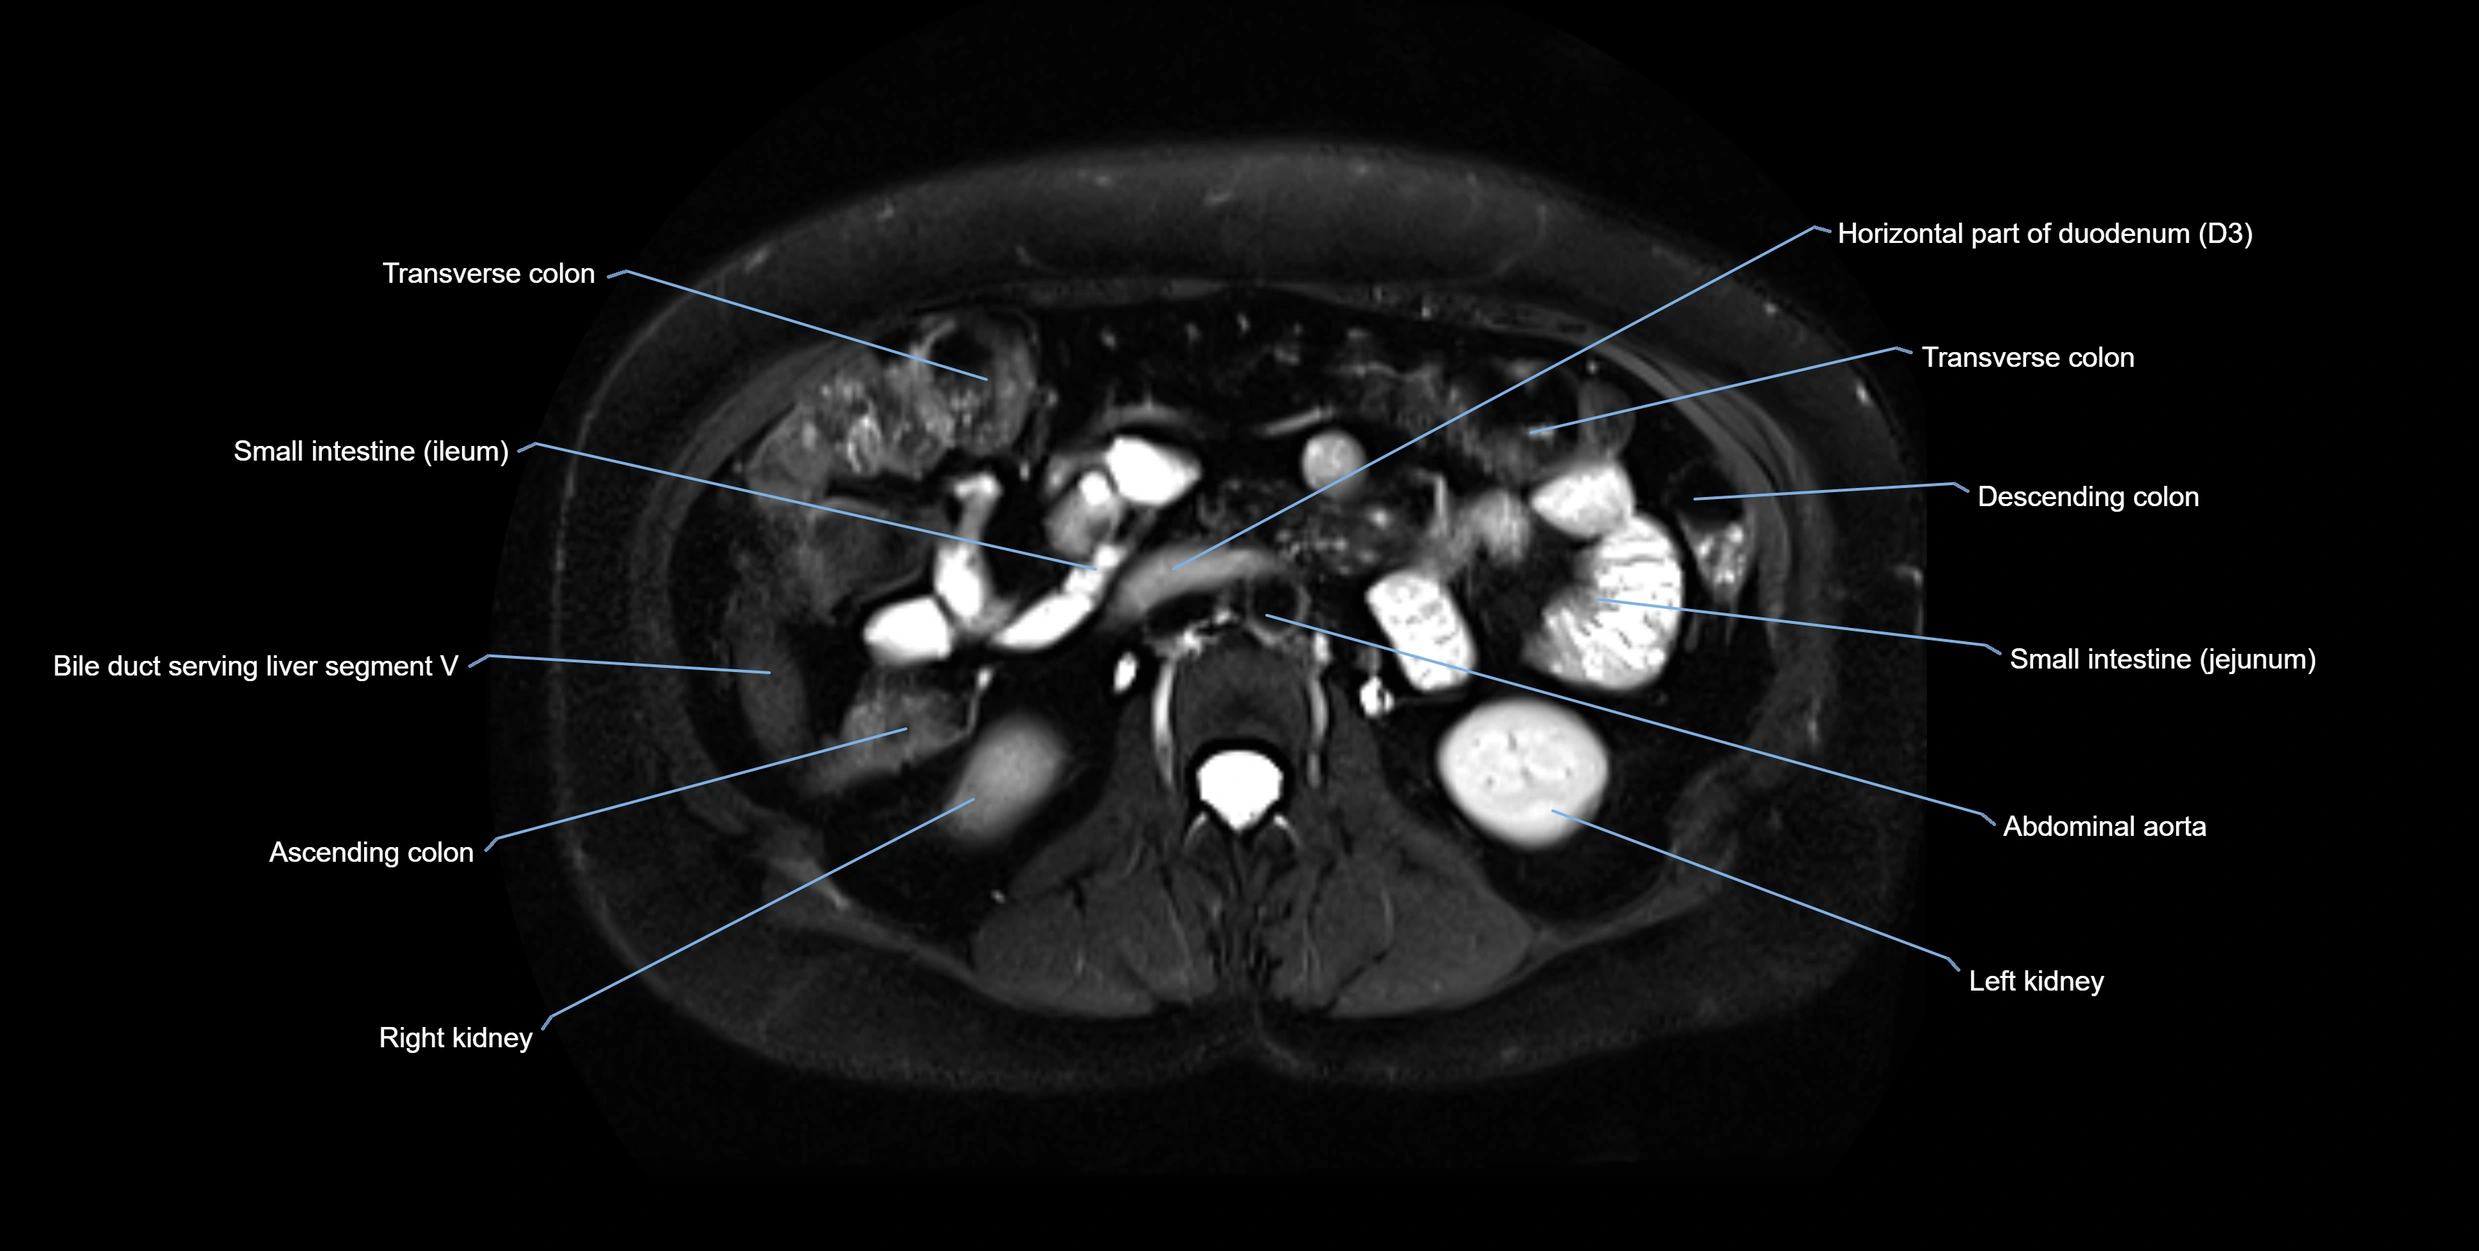

MRI image

image

Fullscreen Image